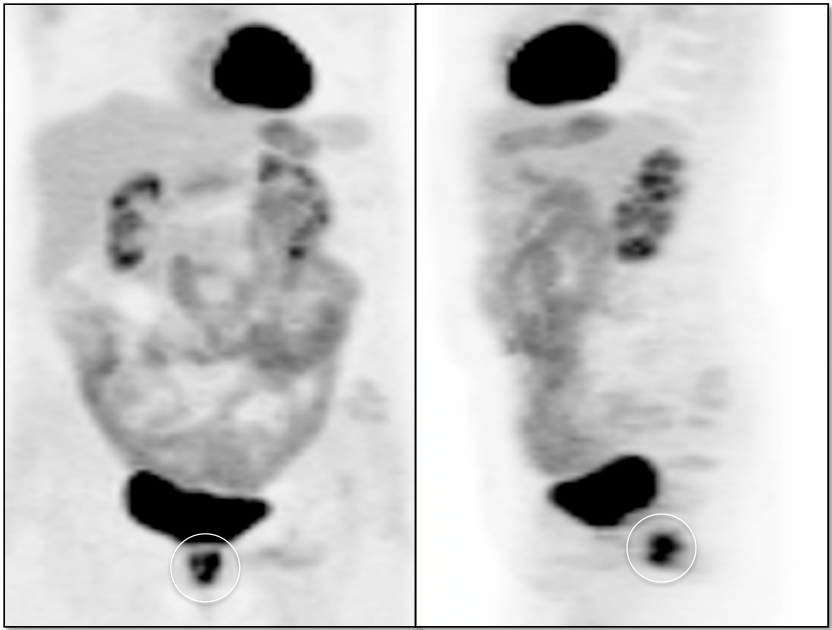

• Beware the small rectal cancer!  As the ano-rectal region frequently demonstrates intense physiologic uptake, it is very easy to overlook a rectal malignancy, especially if it is an incidental finding.  To avoid this error, always evaluate the rectum carefully on the sagittal whole body images.  It is shocking to see how readily apparent a rectal cancer can be on these images, yet so easily overlooked in the axial plane.